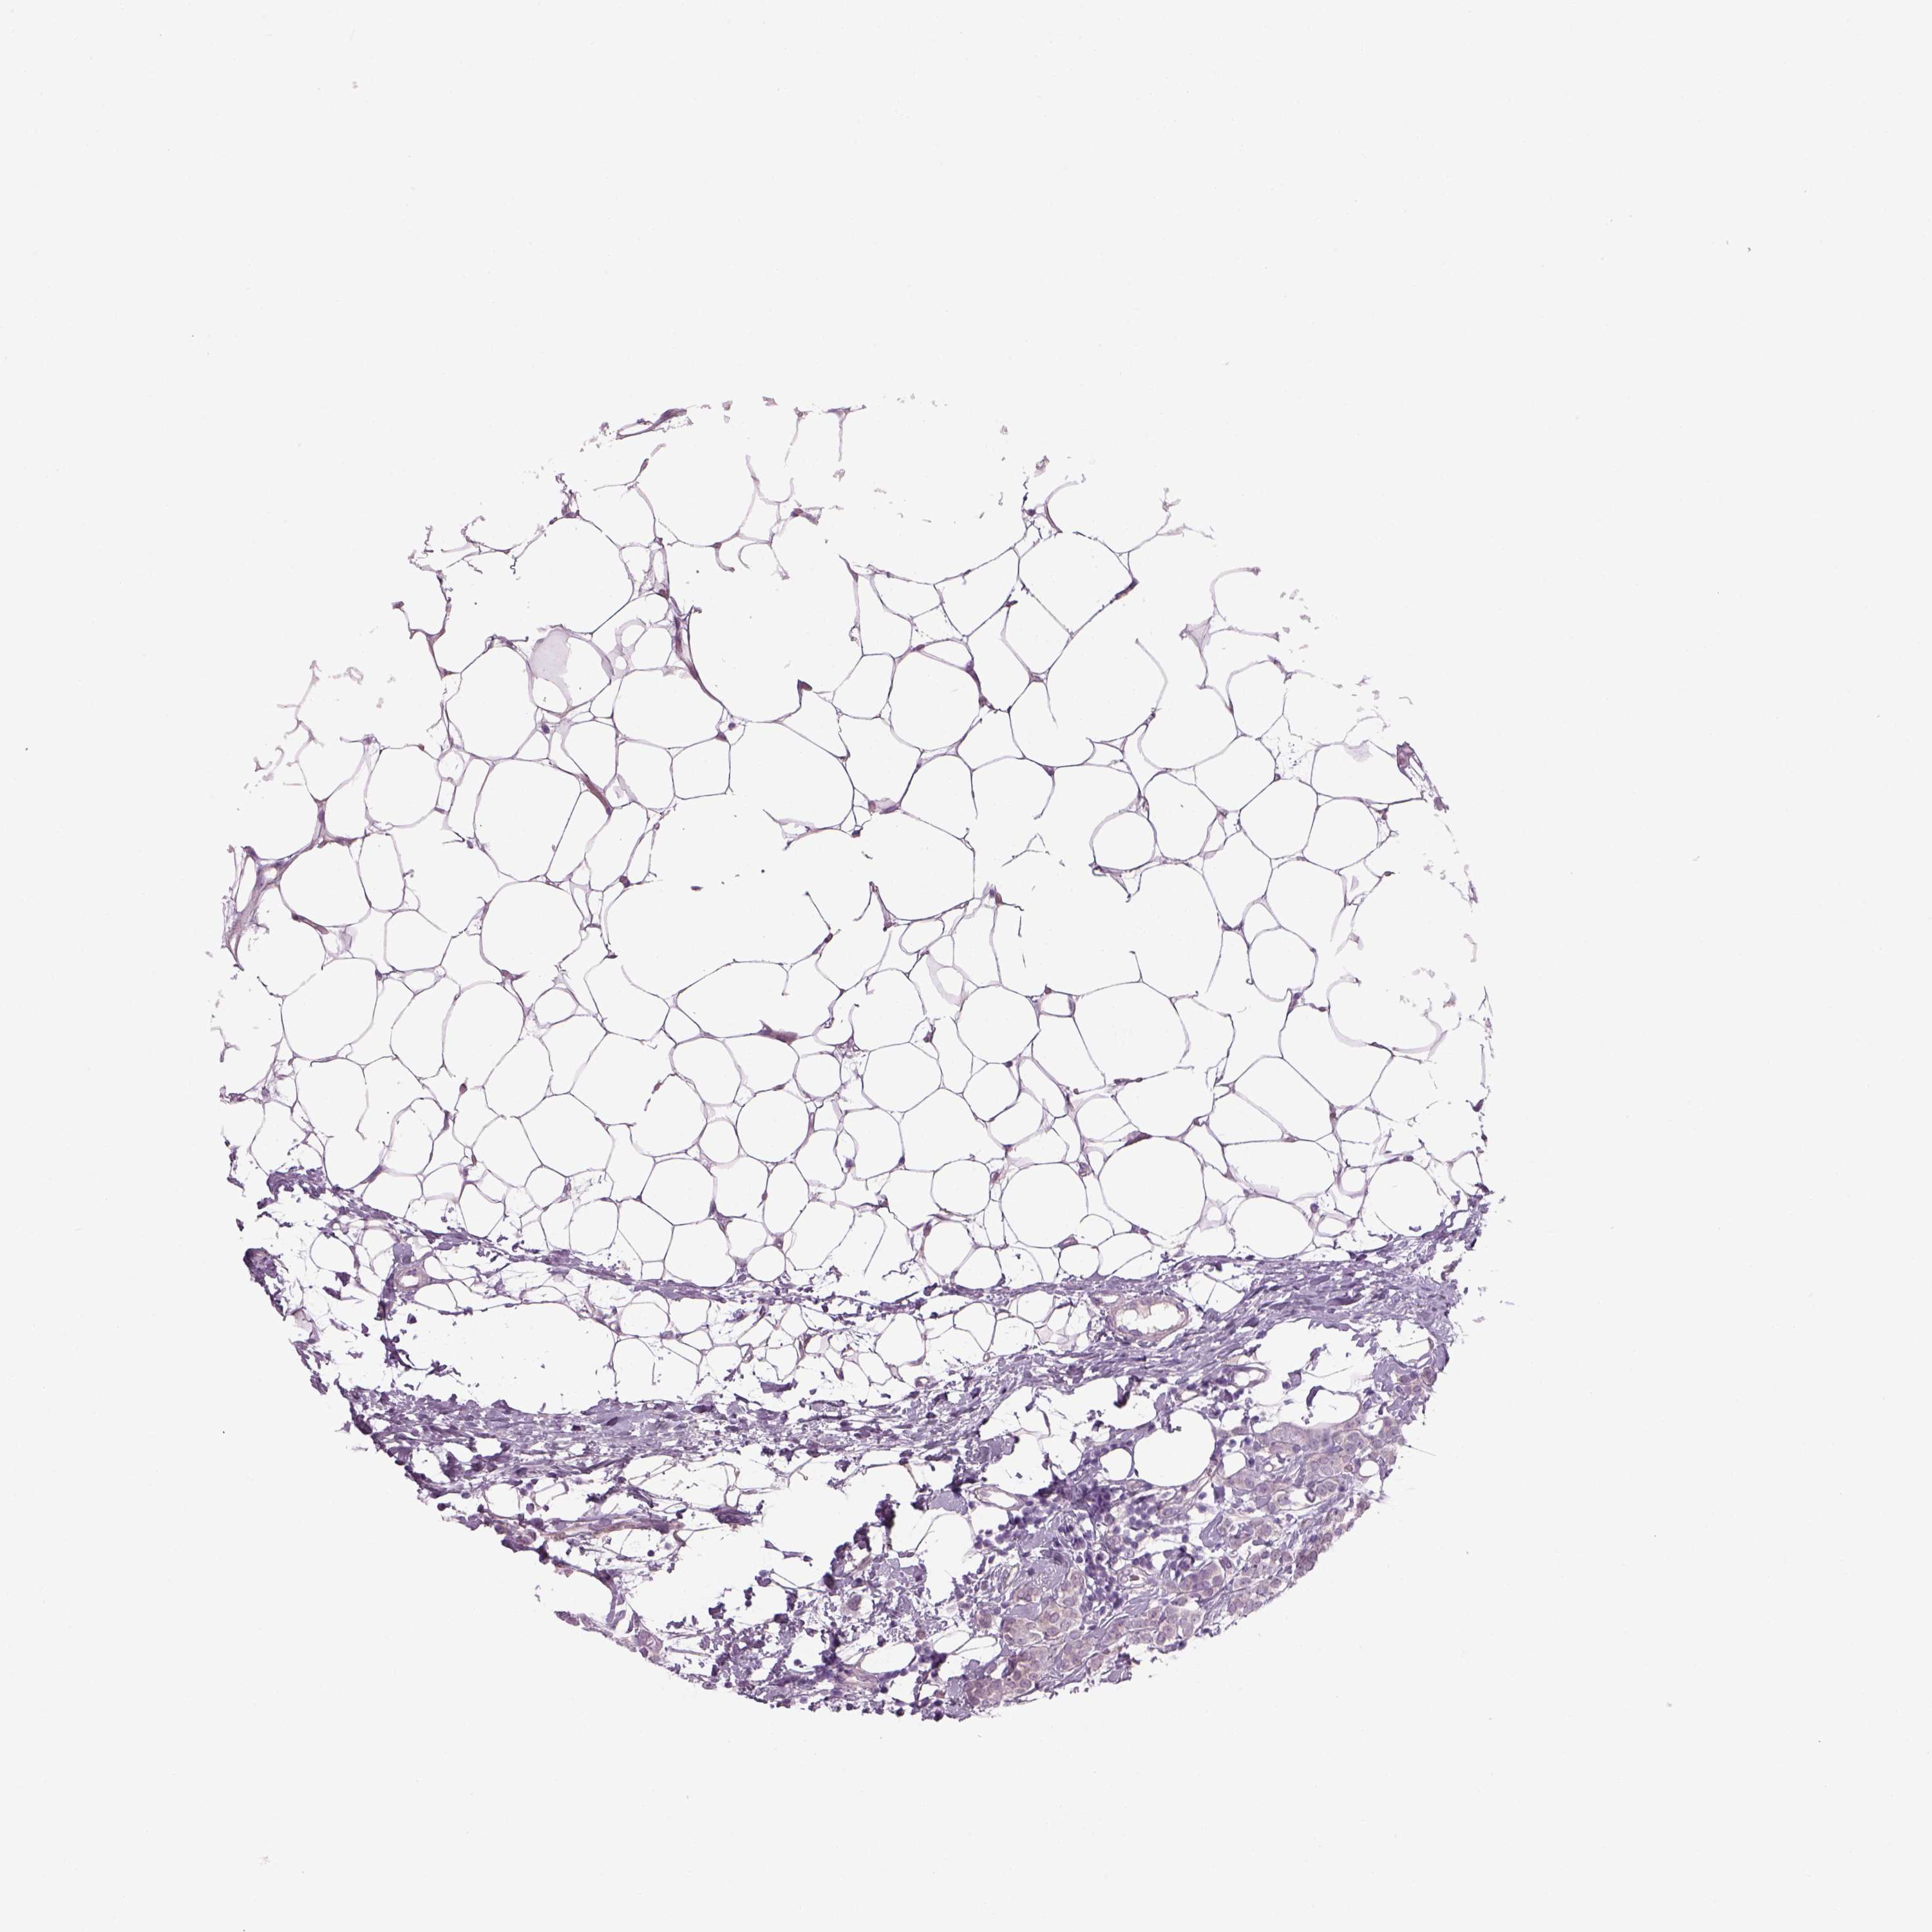

CANCER BREAST CANCER Show tissue menu

Breast cancer

Human cancer